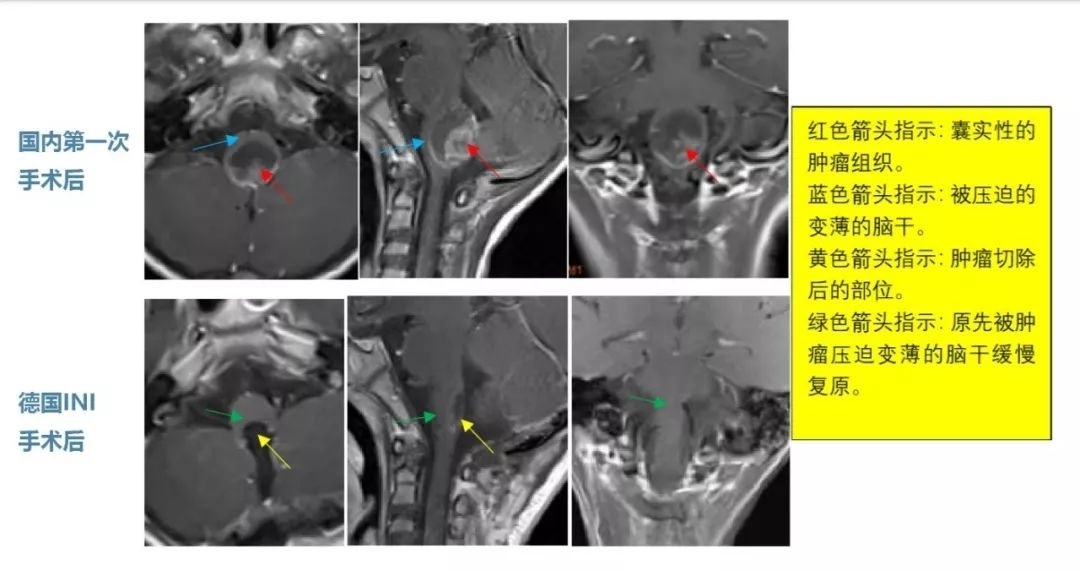

经MRI检查,轩轩被诊断是“四脑室底部占位性病变”。没想到竟是脑肿瘤在作怪,想到如此年幼活泼可爱的孩子还要继续遭受脑肿瘤的折磨,一家人赶紧前往国内某医院做了开颅肿瘤切除术,术后病理诊断为“脑干间变型室管膜瘤WHOIII级”(注:2021年较新世卫组织已取消间变性分级),这是脑肿瘤中恶性程度很高的一种,预后较差,复发率高。

本以为手术切除后,孩子就该慢慢好转起来,但是没想到肿瘤并没有切除干净,术后轩轩的症状丝毫没有见好,救子心切的他们又开始寻求其他治疗方法,在医生的建议下开始了质子刀放射治疗,原本活泼开朗的轩轩在经历了开颅手术后本来就性情转变,连续的放射治疗更让孩子产生了抵触情绪,看着孩子饱受治疗和疾病的双重折磨,轩轩父母看在眼里,疼在心里。但是病魔无情,在接受了一年的质子放疗后,一家人又因为轩轩新的症状遭受了晴天霹雳的打击,孩子开始出现明显的吞咽功能障碍,MRI复查后发现:脑干室管膜瘤又有增长,且已经浸润到脑干右侧很深的部位。希望又一次破灭,1年的放疗起到的作用微乎其微。由于肿瘤较大,位置不同,再次手术的话可能会造成脊髓损伤,很可能出现呼吸衰竭、高位截瘫等严重并发症。国内很多专家都建议保守治疗。

前往德国INI医院,巴特朗菲教授二天就为轩轩进行手术,脑干室管膜瘤被完全切除了,在术中神电设备检测下,术后无新发神经损伤。

在INI术后休养了半个月后,就出院回国了,治疗过程还是顺利的。手术后5个月,孩子吞咽、运动功能恢复地很好,精神状态佳。